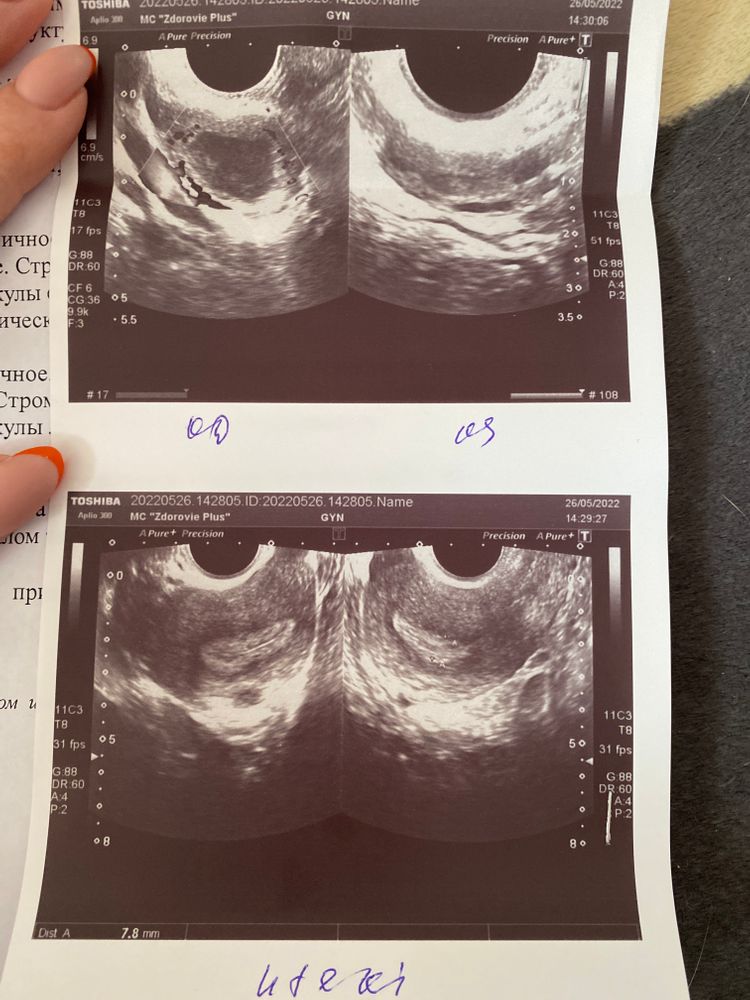

С мужем планируем беременность, сейчас задержка 20 дней, была неделю назад у гинеколога. Сделали узи, беременность не обнаружили, сказали, что в меня эхографический признаки секреторной (лютеиновой) фазы, а месячные так и не пришли. Может по узи можно понять, что со мной?

По УЗИ ничего плохого. Сдайте кровь из вены на общий хгч, если ещё не сдавали. Если результат будет отрицательный - ждите менструацию в течение 10 дней. Она придёт.